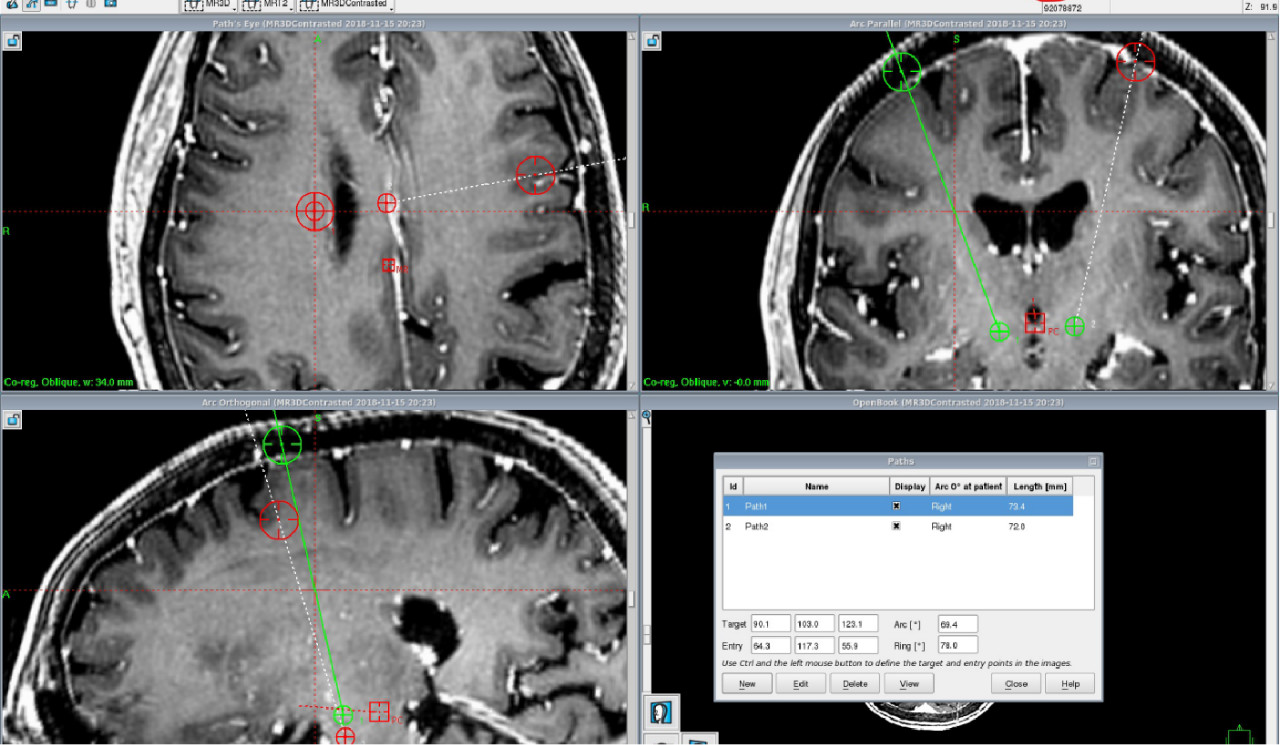

设计电极穿刺路径,确定头皮切口及颅骨钻孔位置。

从脑回穿刺。

避开大脑皮层回流静脉。

避开基底节区穿支血管。

减少出血风险,确保手术安全!

手术过程

微电极记录引导下双侧丘脑底核脑深部电刺激术治疗帕金森病手术视频

核对坐标(double check) 切口设计 植入微电极 MER 植入刺激电极 ITS 全身麻醉 植入IPG 测试系统